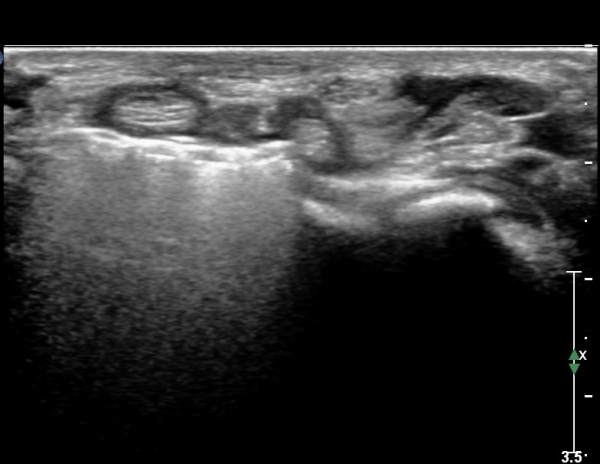

¾Æ·§ÆÈ »óºÎ Ⱦ´Ü¸é°Ë»ç¿¡¼­ Àü°ñ°£ ½Å°æ Áö¹è¸¦ ¹Þ´Â FPL, FDP ¿¡¼­ ½Å°æ¸¶ºñ ¼Ò°ß(°í¿¡ÄÚ ±ÙÀ§Ãà)À»

º¸ÀÌÁö ¾ÊÀ½(»çÁø 1)